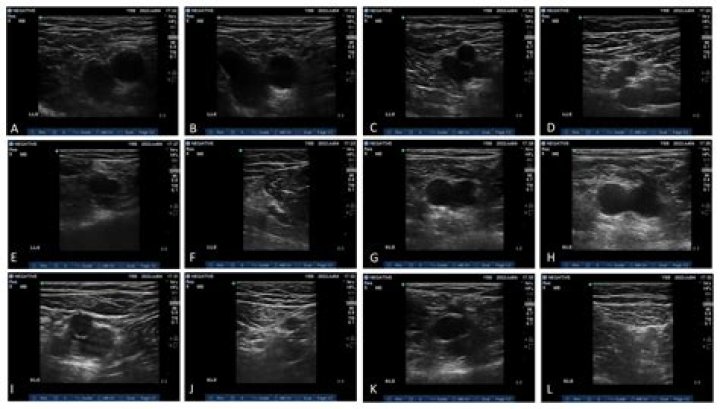

Ultrasound devices have been described as producing therapeutic heating at depths between 1 and 2 half-value depths. 13,23. Therefore, 1-MHz continuous ul...